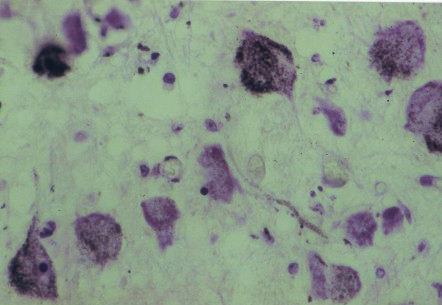

Lichaampjes van Vater Pacini